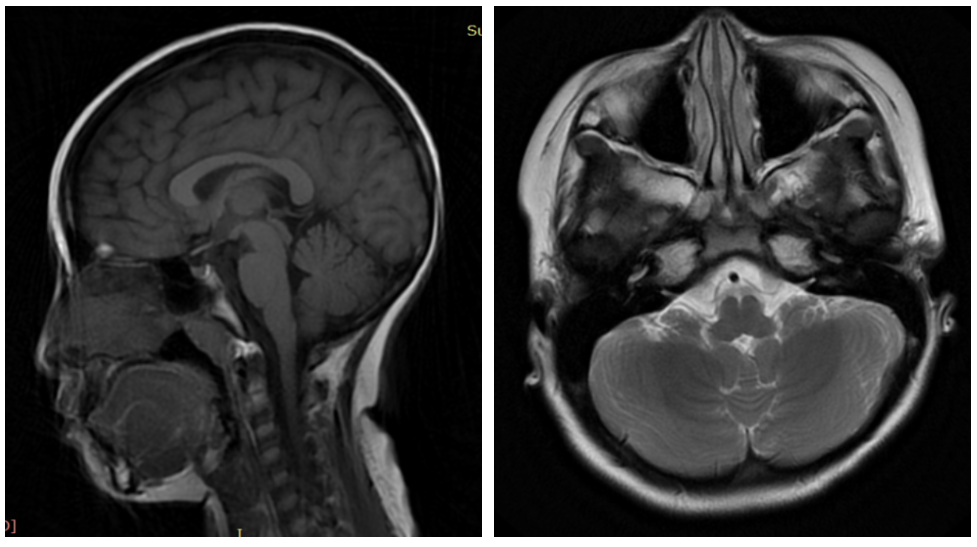

10天后,妮妮夜间突发剧烈头痛伴呕吐,平卧时症状稍缓,急诊检查发现眼底显示瞳孔边缘模糊。腰椎穿刺检测显示脑脊液压力高达320mmH20(儿童正常值为50-100mmH20),确诊为颅内压增高。至8月底,虽然眼压恢复正常,但双眼存在乳头水肿。9月初的眼科检查(包括VEP和OCT)未见明显临床改善,9月11日至17日的头部MRI显示双侧视神经走行迂曲受损,双侧乙状窦变薄,脑室显小。

Di Rocco教授对病例进行详细分析后提出诊断假设:特发性颅内高压(Idiopathic Intracranial Hypertension, IIH),也称假性脑瘤综合征(Pseudotumor Cerebri Syndrome)。该疾病定义为神经影像学无结构性损伤或脑室扩大,脑脊液成分正常,但颅内压升高的临床综合征。普通人群发病率为1/10万,儿童为0.63/10万,育龄肥胖女性高达19/10万。

头痛由颅内压升高引起,通过腰椎穿刺和眼底检查(乳头水肿)证实。可能继发于内分泌异常、感染、维生素摄入、生长激素使用、皮质类固醇戒断、重金属中毒、脑静脉血栓等因素。MRI血管成像显示乙状窦狭窄可能是当前唯一可识别的原因。

2. 脑室偏小机制

颅内水分滞留导致脑组织肿胀,限制脑室扩张。